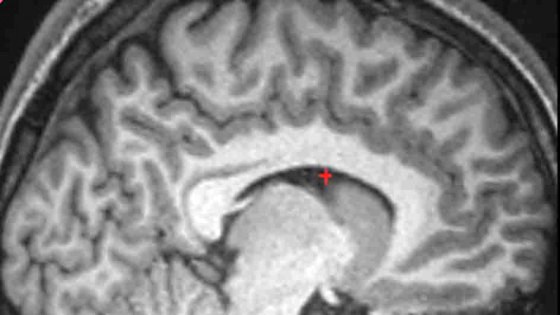

The University of Cambridge scientists found that normal variation in a fold at the front of the brain called the paracingulate sulcus (or PCS) might explain why some people are better than others at accurately remembering details of previous events -such as whether they or another person said something, or whether the event was imagined or actually occurred. The research was published today, 05 October, in the Journal of Neuroscience.

This brain variation, which is present in roughly half of the normal population, is one of the last structural folds to develop before birth and for this reason varies greatly in size between individuals in the healthy population. The researchers discovered that adults whose MRI scans indicated an absence of the PCS were significantly less accurate on memory tasks than people with a prominent PCS on at least one side of the brain. Interestingly, all participants believed that they had a good memory despite one group’s memories being clearly less reliable.